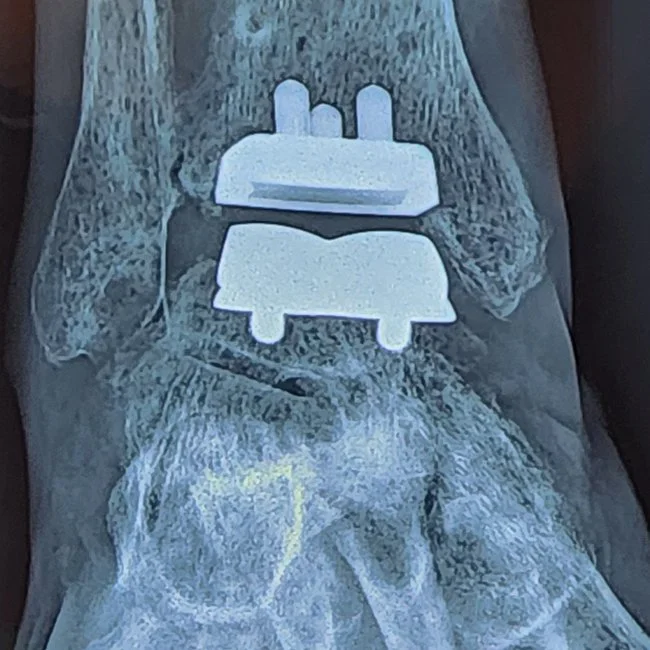

Ankle Replacement Surgery

Significant advances in surgical technique, technology, and prosthesis have made ankle replacement surgery an increasingly viable surgery in the treatment of degenerative and severe ankle arthritis.

Improvements in prosthesis durability and increases in preserved ankle movements are some of the benefits of ankle replacement surgery compared to ankle arthrodesis in treating arthritis and pain.

Associate Professor Roderick Kuo is an expert authority on ankle replacement surgery and has successfully treated many patients with advanced surgical treatments achieving excellent results.